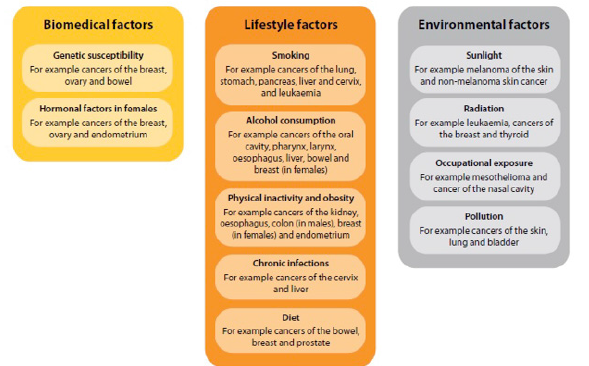

In general, three types of strategic biomarkers are important for PPM- and PPO-related services: Diagnostic, Predictive and Prognostic ones to assess individualized genetic risk prediction tools for a wide array of diseases, and risks, and thus for the national health stability (Figure 6).